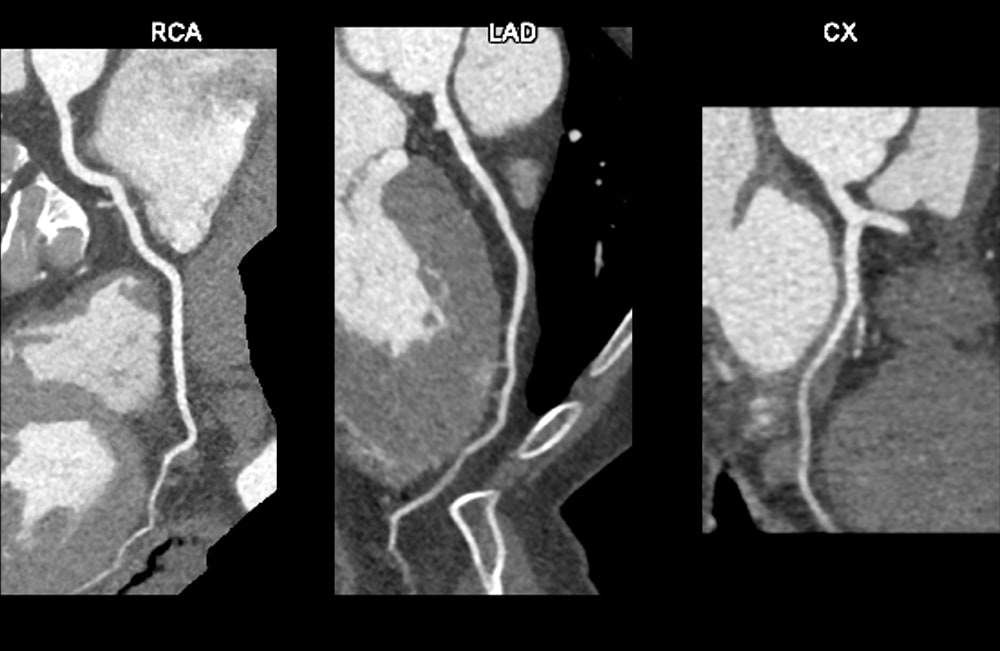

図3.動脈相RCA, LAD, LCX

冠動脈に有意狭窄や動脈硬化性プラークを認めない。